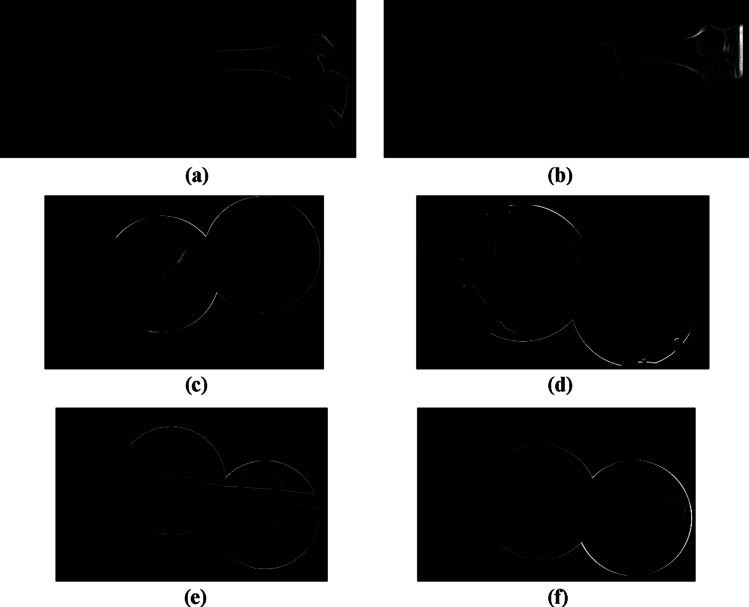

For qualitative comparison of the proposed X-ray image stitching method, the difference between the reference and stitched images is calculated as the margin of error. Since a stitching is conducted on the basis of the first input images, those in the reference and stitched image are initially aligned, and the stitched image obtained using the proposed method is subtracted from the reference image. The difference image is then represented in terms of intensities. Specifically, the reference image is generated by manually adjusting the overlapped input images. Figure 8 shows the difference images for the test images used in the experiments. In each of the difference images, no differences are observed for the first input images as they are aligned before computing the differences. Thus, differences are observed only in the second and third input images. The error from the estimated homography can be analyzed by specifying the difference image, where the edge thickness in the intensity region represents the degree of displacement between the reference and stitched images.

Fig. 8.

Difference images of the test images used in the experiments. (a) X-ray image of a human femur in LAT view. (b) X-ray image of a human femur in AP view. (c) X-ray image of a caprine tibial fracture. (d) X-ray image of a caprine tibia with fixation pins. (e) X-ray image of a caprine tibia with a fixation plate. (f) X-ray image of a caprine tibial phantom